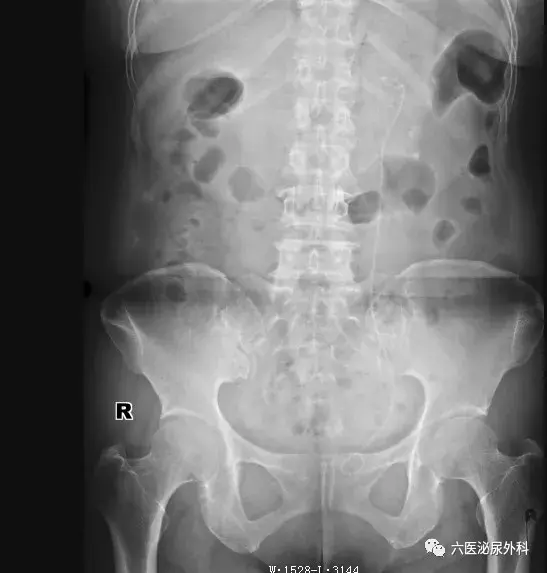

可以看到该患者有三颗结石,一颗位于肾盂输尿管出口处,一颗位于肾中盏,还有一颗位于囊肿内(暂不考虑这颗)